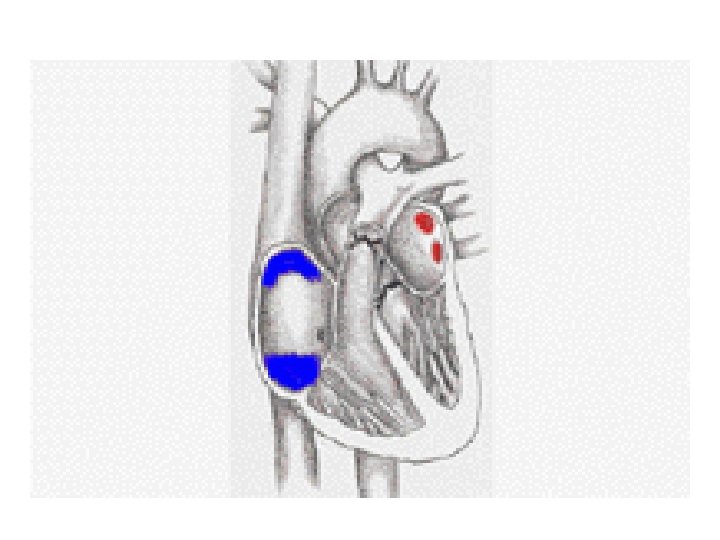

• Remember that the left side (RED) accepts and pumps out oxygenated blood. • The right side of the heart (BLUE) accepts and pumps out deoxygenated blood.

OXYGENATED BLOOD • This is blood that is rich in oxygen because it has recently left the lungs where the process of gaseous exchange occurred in order for the oxygen to diffuse into the blood vessels. • The LEFT side of the heart pumps oxygenated blood which is very red.

DEOXYGENATED BLOOD • This is blood that is depleted of oxygen because it has travelled around the body supplying the body cells with the oxygen. • The RIGHT side of the heart pumps deoxygenated blood which has a slightly blue colour.